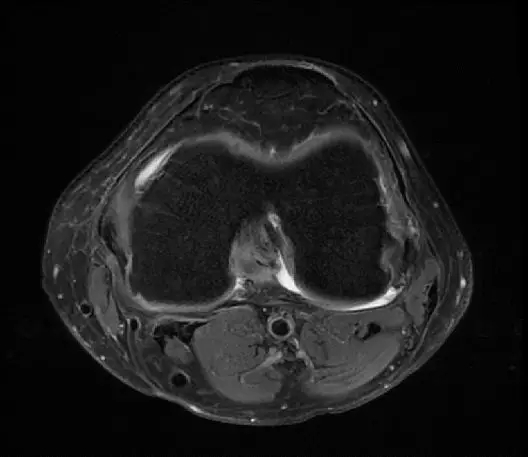

后交叉韧带断裂

从此片可以看出后交叉韧带连续性中断,松弛,增粗,下止点信号增高比较明显,从这个角度看后交叉韧带上止点信号较为正常,但下止点信号明显增高,缺乏韧带止点应有的形态,从这个层面看下止点信号增高,从这个层面看韧带是增粗的,整体信号增高,质地不均一,并且松弛,从这个层面可以看到它的下止点信号增高,缺乏正常的韧带形态特点,所以考虑后交叉韧带断裂。